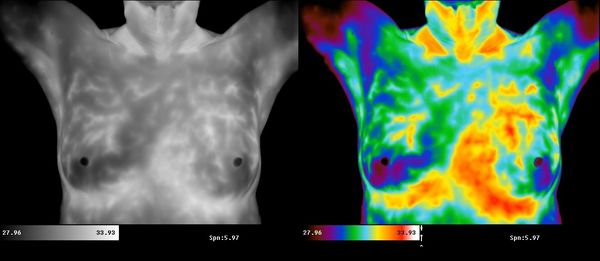

Thermal imaging is the only tool that gives you an inside look into the physiology of your breasts, giving patients a risk-assessment of disease years before tumors can form. Our goal is to provide insight into your body to help you take control of your health choices.

Thermography is an FDA approved technology used to identify physiological signs that precede cancer and signal future risk. Many believe they can improve, modify and manage their risk through lifestyle changes, diet, and natural treatment. Thermography offers patients a tool for monitoring the effectiveness of these treatments.

Studies show high levels of estrogen are a key risk factor for breast disease. Thermography can offer your physician a powerful diagnostic tool to identify Breast Specific Estrogen Dominance.

Breast infrared thermal imaging is a cornerstone to detecting breast disease at its earliest stages. When combined with mammography and a clinical breast exam - your chances of detecting breast disease is substantially increased.